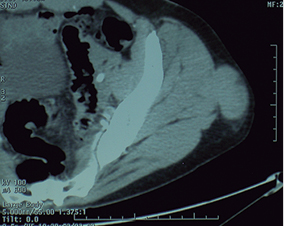

Paciente femenina de 49 años de edad, ama de casa, deportista de alto nivel (realiza tres horas diarias de ejercicios aeróbicos desde hace 10 años). Acudió a rehabilitación el 3 de enero de 2013 por presentar dolor moderado en la zona lateral de la nalga izquierda de tres meses de evolución, manifestado durante la carrera; reportó aumento de volumen de la zona mencionada. A la exploración, se observó aumento de volumen discreto por arriba del trocánter mayor, correspondiendo a masa no dolorosa de consistencia firme, de 5 × 4 cm, fija a planos profundos, dependiendo del músculo glúteo medio por desplazarse con él durante la abducción de la cadera; los arcos de movimiento articular de los miembros pélvicos fueron normales. Al examen clínico muscular: músculos de MI calificados en 5/5 bilateral; reflejos y sensibilidad, normales. Con los datos anteriores, se efectuó el diagnóstico de tumor de tejidos blandos, por lo que se solicitó TAC de abdomen y pelvis, la que mostró presencia de una lesión ocupativa dependiente del músculo glúteo medio izquierdo, con extensión a tejido celular subcutáneo adyacente, con diámetros de 4.7 × 3.8 cm, isodensa, de contornos lobulados bien definidos, con reforzamiento posterior a la administración de contraste endovenoso (Figura 1); abdomen normal. Ultrasonido de la región: se identificó un conglomerado ganglionar en la región inguinal superficial, el mayor con dimensiones de 2.4 cm; este no mostró vascularidad anormal con Doppler color; retroperitoneo sin adenomegalias. Se canalizó a oncología, con el diagnóstico de sarcoma; se le realizó biopsia incisional; se documentó sarcoma fibromixoide y, en un segundo tiempo, se efectuó resección amplia de la lesión. El reporte histopatológico mostró un espécimen irregularmente ovoide que correspondía a músculo estriado, con dimensiones de 4.5 cm de eje principal, fibroso y de color rojizo; microscópicamente, proliferación de células redondas y ovoides de manera difusa con patrón mixoide, que carecían de atipias y mitosis, alternando con sitios que constituían nódulos, que contenían células redondas dispuestas en hileras con abundantes haces de colágena hialina; las células proliferantes tenían citoplasma pálido y, en algunos sitios, eosinófilo; su núcleo era grande, nucléolos prominentes; en escasos sitios, las células mencionadas mostraban el núcleo lobulado e hipercromático y mitosis promedio de cinco por cada 20 campos a seco fuerte; en cortes de la zona periférica se identificó colágena hialina que contenía trabéculas de hueso metaplásico. Los bordes de sección quirúrgica, libres de actividad neoplásica; con diagnóstico de sarcoma fibromixoide de grado histológico bajo (Figura 2). El estudio inmunohistoquímico mostró CD-10, enolasa neuroespecífica y proteína S-100 negativas, con vimentina positiva, lo que apoyó el diagnóstico de sarcoma fibromixoide de los tejidos blandos. En ese momento, se catalogó en estadio IA (T1bN0M0).

Figura 1: Tomografía computada, corte axial a nivel pélvico, mostrando lesión ocupativa dependiente del músculo glúteo medio izquierdo, isodensa, de contornos bien definidos, con diámetros de 4.7 × 3.8 cm. Histológicamente, correspondió a un sarcoma fibromixoide de bajo grado en una paciente femenina de 49 años.